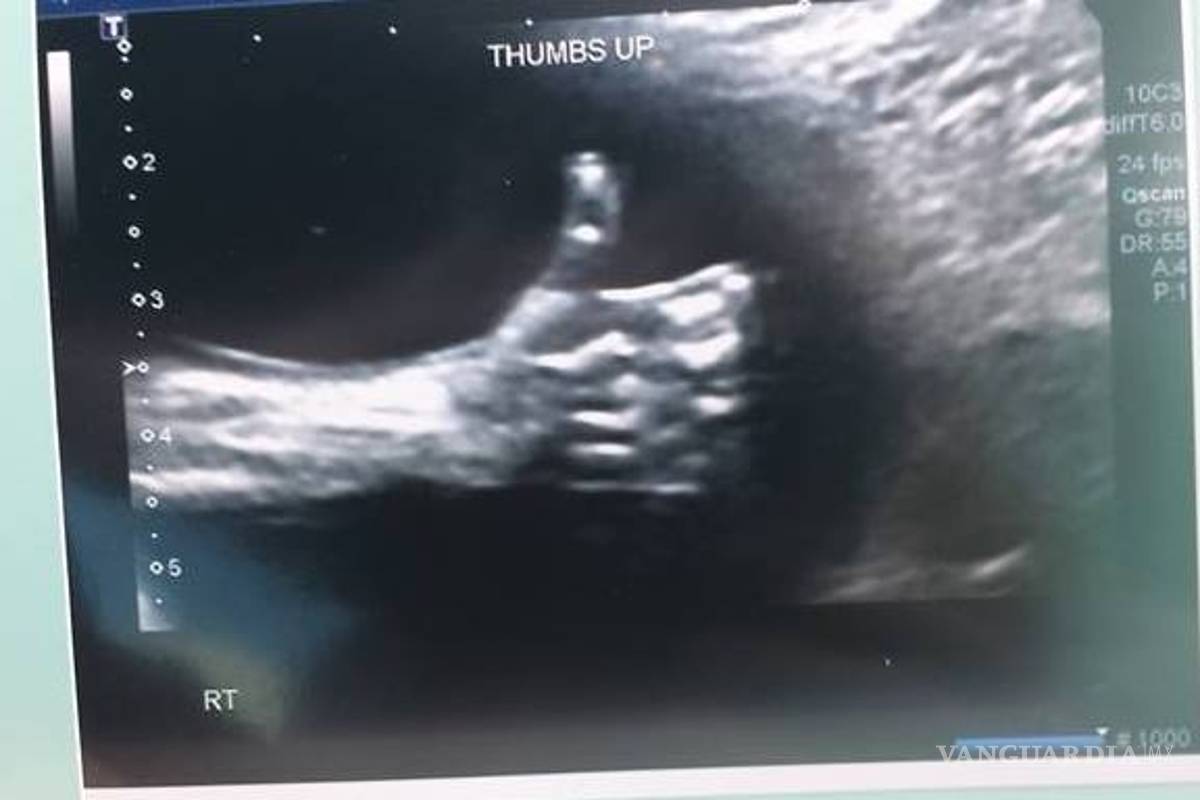

Nicole Kim, la madre, encontró este inspirador mensaje en la ecografía de la semana 20: un pulgar para arriba

Nicole Kim, la madre, encontró este inspirador mensaje en la ecografía de la semana 20: un pulgar para arriba. Kim contó en la web del programa Today, de la NBC, que el mensaje del bebé llegó justo cuando su padre, Tony, lo acababan de echar del trabajo.

En una entrevista con el Calgary Herald, Kim contó también que el técnico de la clínica de Calgary donde hizo la ecografía le dio rápidamente al zoom y tomó la foto cuando vio al bebé con el pulgar levantado.